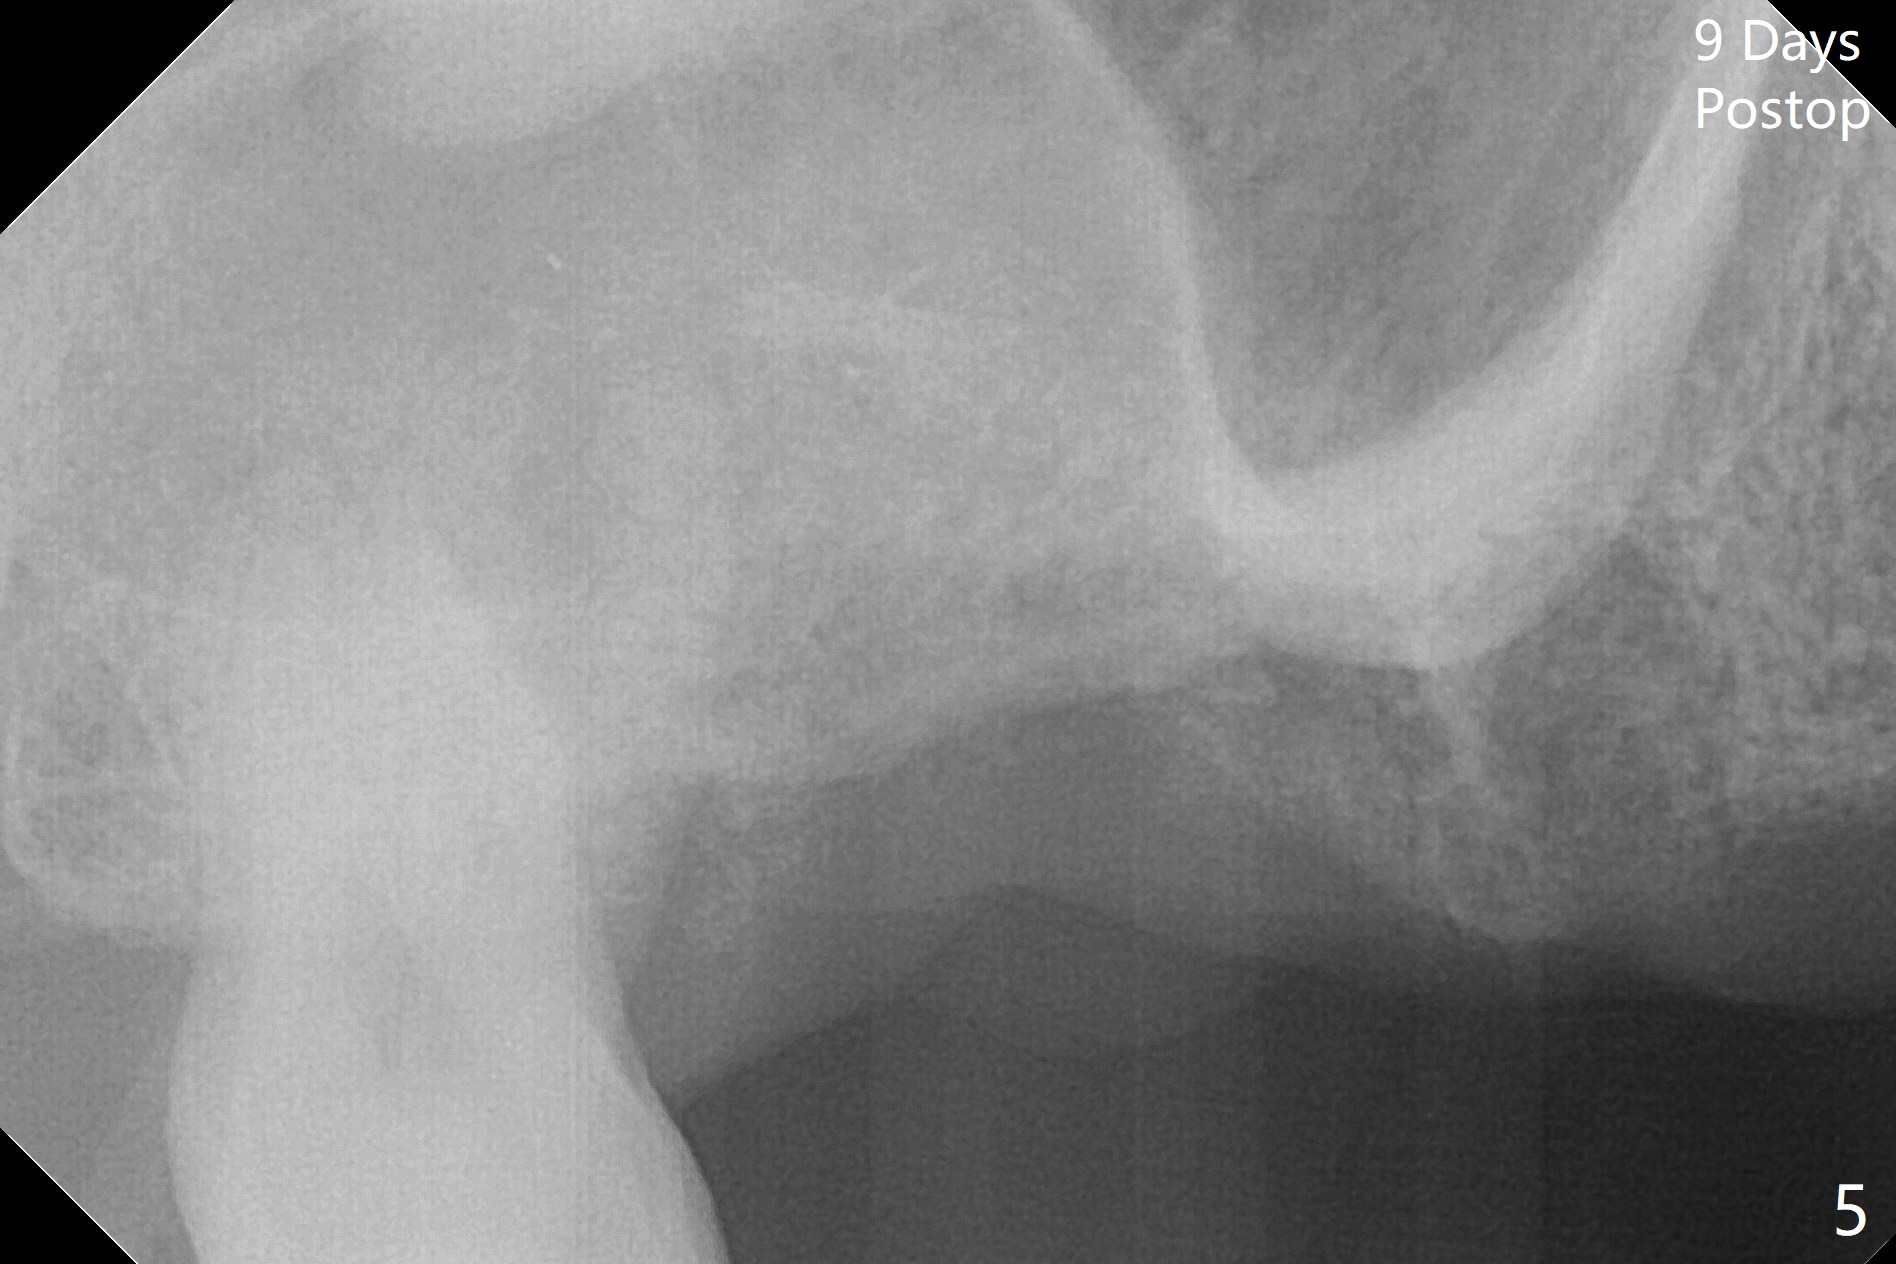

A 57-year-old woman returns with pain in the upper right quadrant (Fig.1,2). In fact the mesiobuccal root of the tooth #2 has vertical fracture. Although the socket destruction at #3 is not as extensive as that of #2, the socket of #3 has communication with the sinus. Prior to socket preservation, a piece of Osteogen plug is inserted at #3. PRF should be prepared for severe bone loss. In contrast there is no bone loss around the implants at #19 or #30 (Fig.1,3,4). Although the socket at #2 is slightly open 9 days postop, bone graft appears to be present (Fig.5). The bone at #2 and 3 seems to regenerate 7 months post socket preservation (Fig.6). Three short implants seem to be better than 2 implants for 3-unit FPD (Fig.7-9).